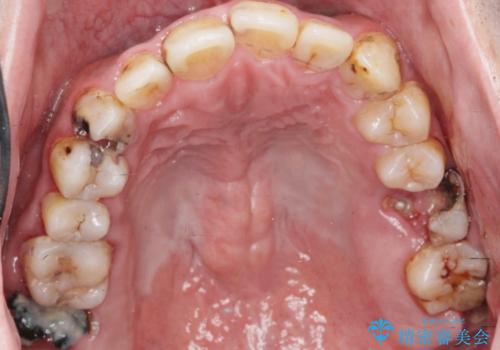

[メタルフリー] 虫歯・銀歯だらけの口腔内を全顎治療

![[メタルフリー] 虫歯・銀歯だらけの口腔内を全顎治療の症例 治療前](https://seimitsushinbi.jp/wp/wp-content/uploads/2025/03/e26a9887bc6905a2f0f51f5772b5ac9c-500x350.jpg?v=1741918285)